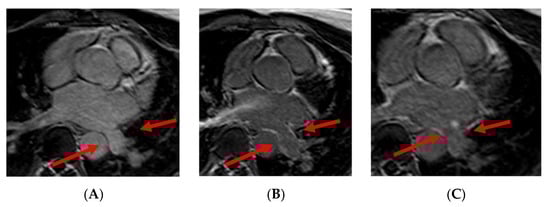

3.5. Atrial Thrombus Assessment

- Kitkungvan, D.; Nabi, F.; Ghosn, M.G.; Dave, A.S.; Quinones, M.; Zoghbi, W.A.; Valderrabano, M.; Shah, D.J. Detection of LA and LAA Thrombus by CMR in Patients Referred for Pulmonary Vein Isolation. JACC Cardiovasc. Imaging 2016, 9, 809–818. [Google Scholar] [CrossRef] [Green Version]